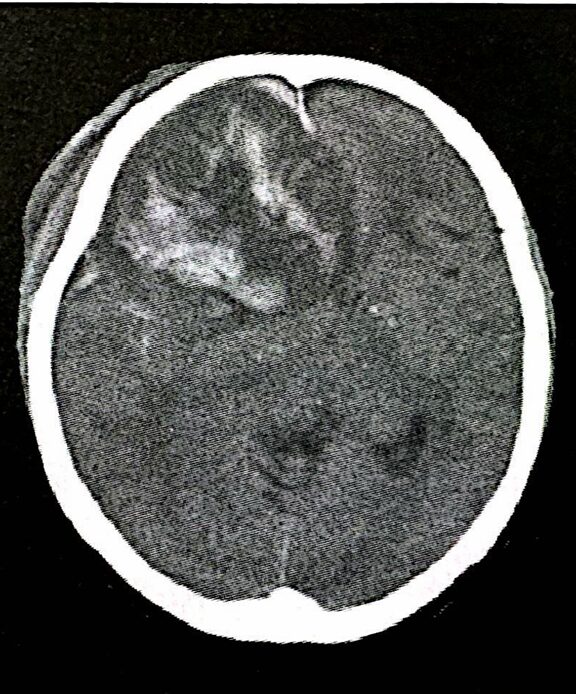

脳挫傷(Brain Contusion)

頭部への強い衝撃により、非可逆的に脳の挫滅が限局性、もしくは多発性に起きる状態です。挫傷の度合いにより脳内出血のようになります。症状としては、意識障害や強い頭痛、嘔吐・嘔気、痙攣などです。通常、検査は簡便で短時間で施行可能なCT検査が優先されますが、非出血性の脳挫傷や小さい脳挫傷に関しては、CT検査よりもMRI検査の方が発見率は高くなります。

脳挫傷は受傷から数時間徐々に増大する恐れがありますので、診断後は入院が必要になります。入院後は頻回の頭部画像検査にて挫傷の度合いを観察します。挫傷や出血量が多く、生命予後にかかわる場合は開頭による手術が必要になります。